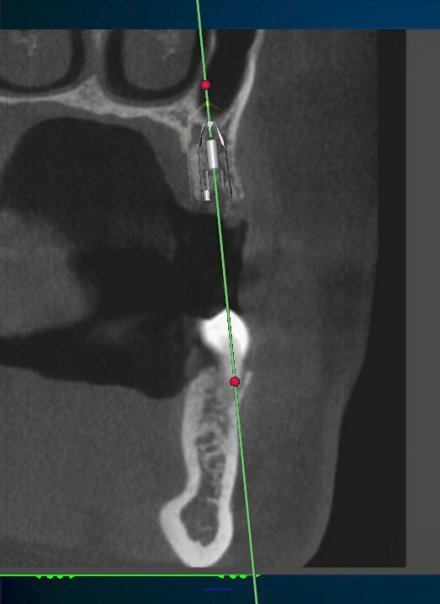

CT Planning For Upper Jaw Implant